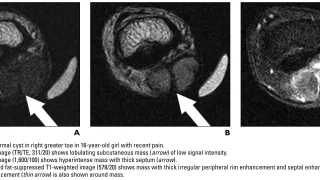

午前の病院での仕事今朝は, 曇.雲が厚く, 部屋の中が薄暗かったので, 電灯を点けました.雨の予報ですが, 午後には上がるとのこと.8時前に病棟に上がって, 8時から朝の病棟回診.昨日, 足関節部の神経鞘腫を摘出した患者さんは, つま先を曲...